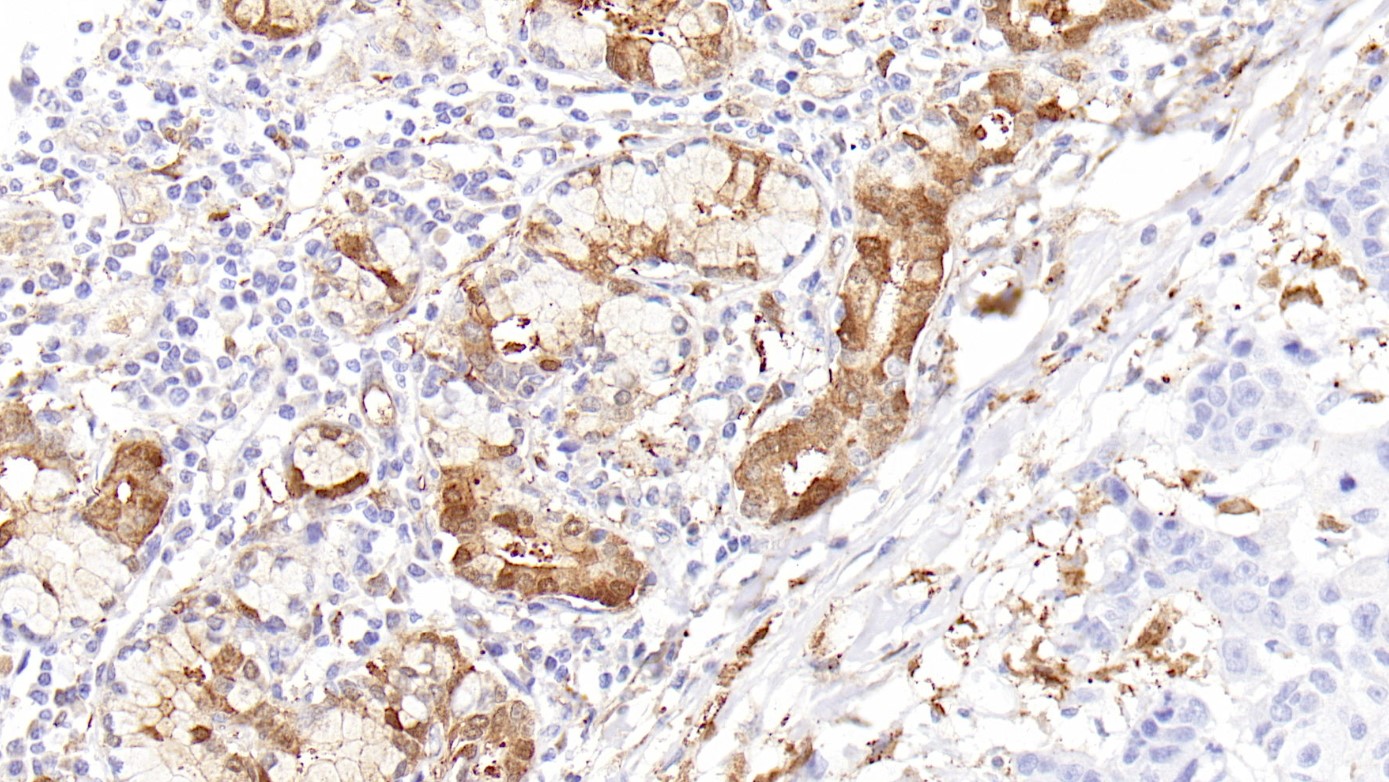

2.Serum calretinin as an independent predictor for platinum resistance and prognosis in ovarian cancer.[J]. Link Theresa,Passek Simon,Wimberger Pauline,Frank Kerstin,Vassileva Yana Damyanova,Kramer Michael,Kuhlmann Jan Dominik. International journal of cancer. 2020(9)